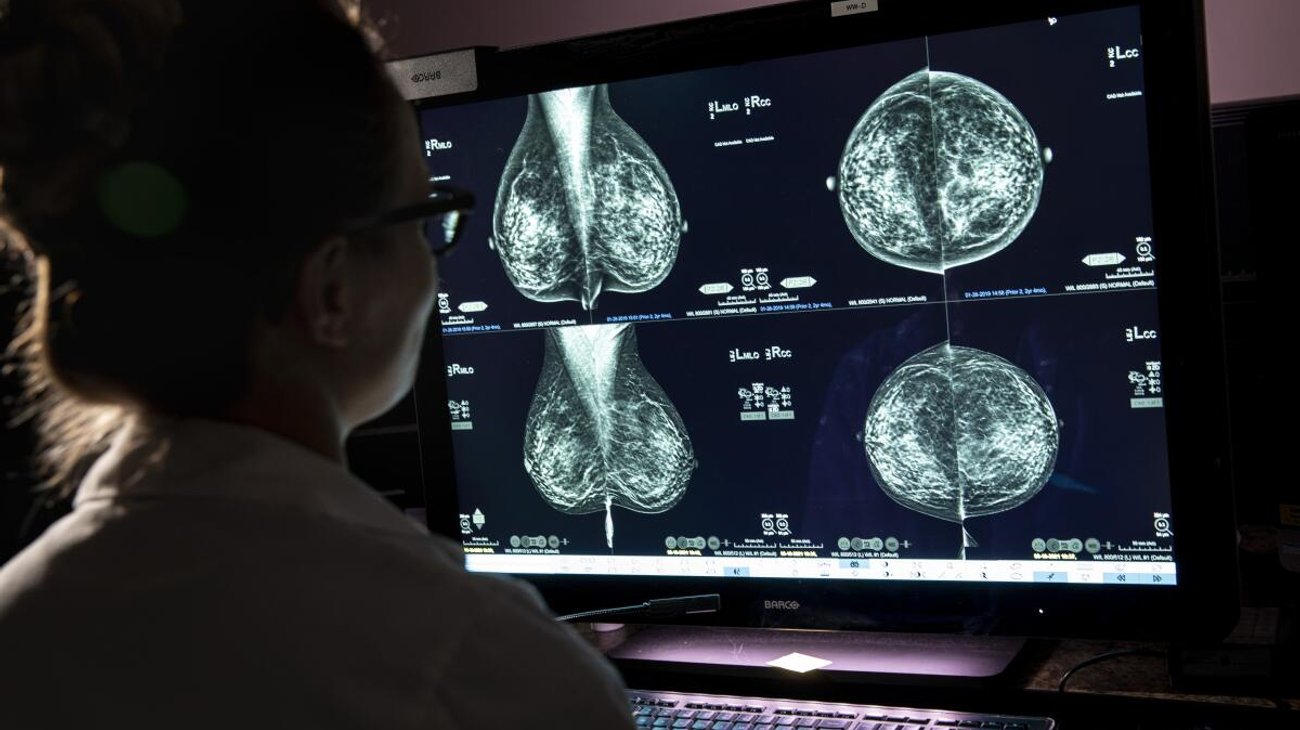

Un fallo de información en el sistema para la detección precoz del cáncer de mama en Andalucía, España ha provocado que más de 2,000 mujeres no fueran informadas de resultados sospechosos, en un caso que las pacientes califican de "negligencia" de las autoridades locales.

Se trata de un fallo de información en el programa de cribado de cáncer de mama de la región andaluza, que ha provocado que a 2,000 mujeres que se hicieron las pruebas y les salieron como "dudosas" o "no concluyentes" no les llamaran para informarles.